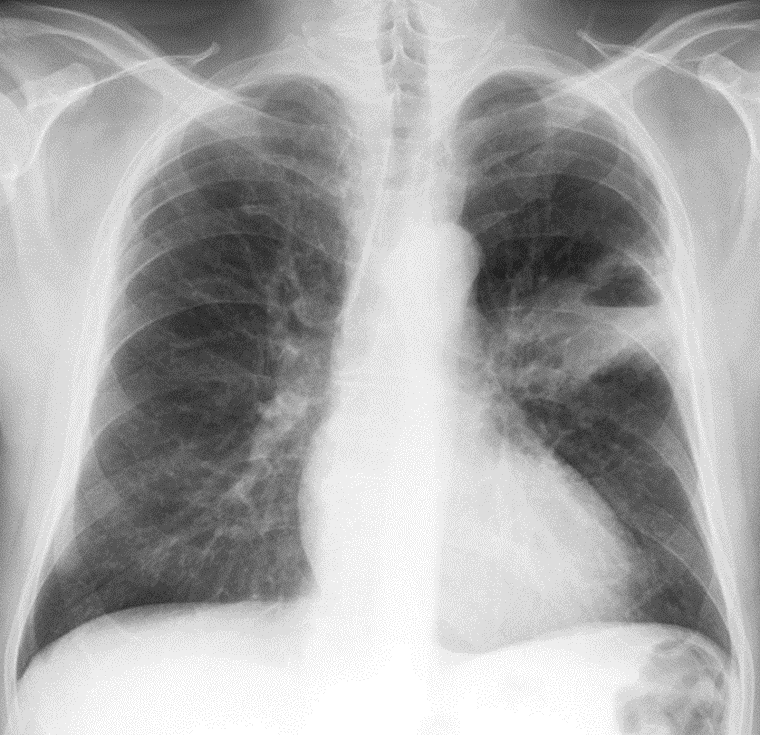

1-U thùy trên phổi (T) hoại tử